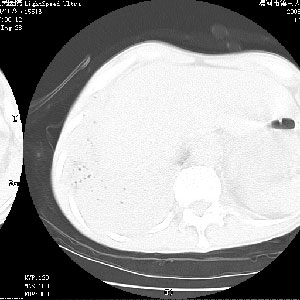

m 老年 发烧、呼吸困难,慢支、肺气肿多年;记的那次是下午大概17:38做的,晚上窒息死亡。

上面的层面就慢性支气管炎肺气肿、肺大泡,别的没有什么、也就不传了。

当时我怀疑:1、阻塞性肺不张早期 2、肺脓肿早期,望老师们发表意见

病灶边缘清---多个含气小腔---近端未见通畅气管影-----支持-----慢性肺脓肿继发阻塞性肺不张

阻塞性肺不张原因-----脓液未排出

3、细支气管肺泡癌可以排除,病变以斜裂为界,呈大片状高密度影,内可见多发小气泡,表明有产气杆菌感染所致,内无明显的支气管“枯树枝征”表现,再结合其临床改变(细支气管肺泡癌临表表现重、影像表现轻)所以不符合细支气管肺泡癌(炎症型)的改变。

病变按肺叶分布,病变内可见多个小空腔影,未见充气支气管影,中间段支气管管腔肺窗示密度欠均匀,下肺支气管分叉处基底段支气管隐约可见,未见明显狭窄,中叶支气管通畅,

考虑:阻塞性肺炎伴小脓肿形成可能性大。(痰栓可能性大)

右下肺实变,内有弥漫分面小气泡而无支气管征,叶间裂前移,呈臌大之形,而无收缩之状,兼纵隔稍左行移,故。不支持不张,倒支持大叶肺叶,如楼上所说,小气泡不象残留之肺,不可以考虑产气菌感染吗。

阻塞性肺炎,肺脓肿形成。依据,右下支气管不通,大片实变形内可见小气泡。不支持肺不张。